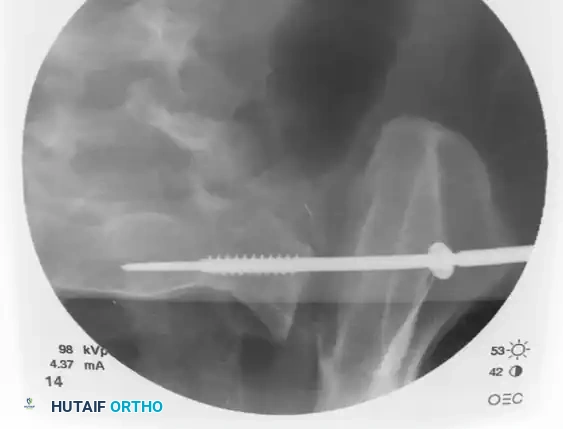

Finally, check the lateral sacral view to ensure that the guidewire is entirely contained within the osseous boundaries of the sacral body and has not breached the anterior alar slope.

Image

Step 4: Drilling and Measurement

With the guidewire safely positioned in the S1 body (or extending into the contralateral S1 body if a trans-sacral screw is planned), measure the required screw length using a cannulated depth gauge.